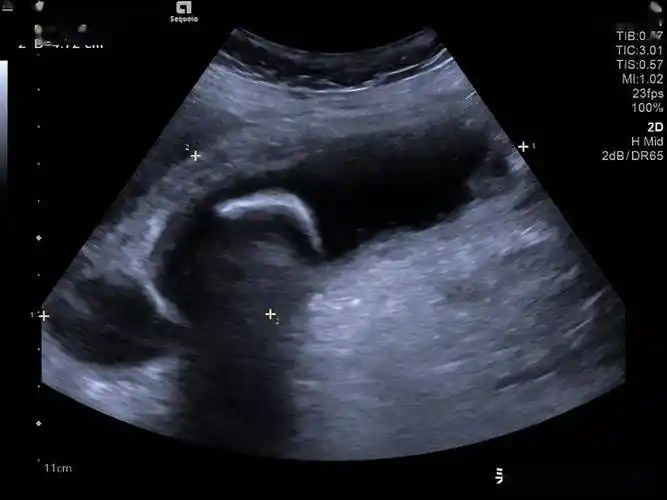

高危老年胆囊炎患者救治 介入超声解难题_引导_肝脏_胆汁